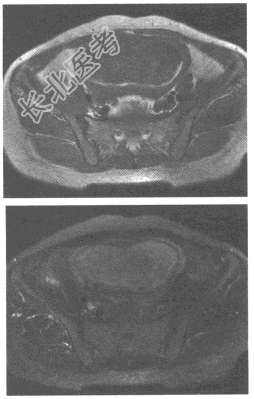

- 单项选择题女性,35岁, 停经2个月,血HCG明显升高。盆腔MRI图像如下, 最可能的诊断为

A、葡萄胎

B、子宫内膜癌

C、子宫出血

D、子宫腺肌症

E、以上都不是